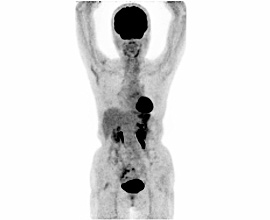

悪性結節性汗腺腫

20年前右下腿を裂傷、他院にて縫合手術施行。10年前より同部位にしこりを自覚し徐々に増大し色調変化及び硬結を認めた。腫瘍を疑い局所麻酔下にて切除を施行した。

病理診断結果は、エクリン汗腺由来の悪性結節性汗腺腫であった。

PET-CT画像